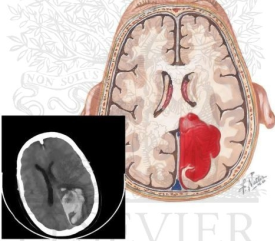

吐血整理|颅内出血影像学表现总结(上)

吐血整理|颅内出血影像学表现总结(下)